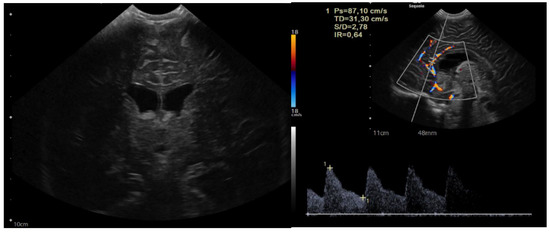

In spectroscopy sequences an elevated choline peak and low N-Acetylaspartate (NAA) and creatine, were found, suggesting an ATRT (Figure 3). No leptomeningeal dissemination was found.

Figure 3.

Spectroscopy analysis showing an augmented rate of choline, in favor of a malignant lesion.